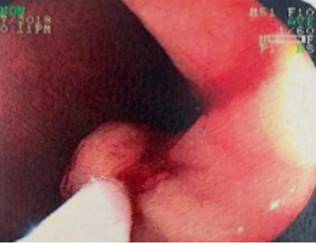

Se utilizó una torre de endoscopia estándar, con esofagogastroduodenoscopio de un solo canal de trabajo. Se utilizó una aguja de esclerosis con solución de adrenalina 1:20 000 para infiltrar la lesión en su base y se practicó una resección endoscópica con un asa poligonal, con la que se logró recuperar una sola pieza completa, de aproximadamente 12 mm de dimensión mayor (Figuras 3 y 4).